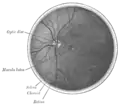

شكل تشريحي لعين عجل

جزء من العصب البصري وداخل مقلة العين, مقطع عرضي.

جزء خلفي من مقلة العين اليسرى.